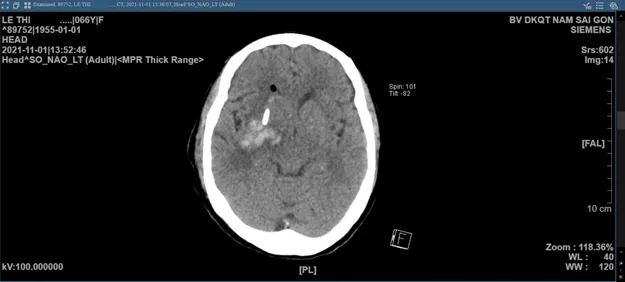

Sau khi được phẫu thuật bằng phương pháp định vị 3 chiều Navigation trong phẫu thuật xâm lấn tối thiểu, bệnh nhân hồi phục cực kỳ nhanh chóng. Sau 3 ngày dẫn lưu và chụp lại CT sọ não, máu tụ trong não chỉ còn lại rất ít, người bệnh đã hoàn toàn tỉnh táo và nói chuyện bình thường, không còn dấu hiệu liệt mặt và chân tay đã cử động gần như bình thường. Sau 7 ngày bệnh nhân đã xuất viện và tiếp tục tập vật lý trị liệu tại nhà.

Hình ảnh CT sọ não sau phẫu thuật